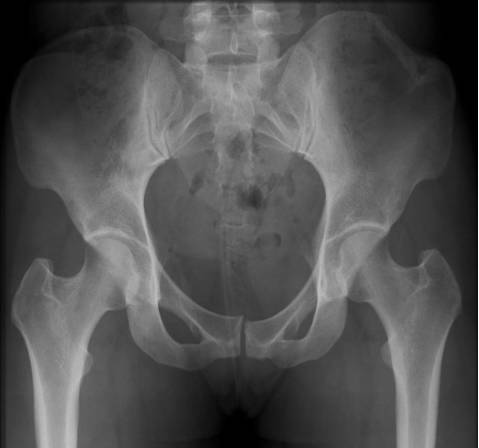

Pipkin骨折

股骨头骨折伴髋关节后脱位。常见于屈膝屈髋位汽车仪表盘损伤。